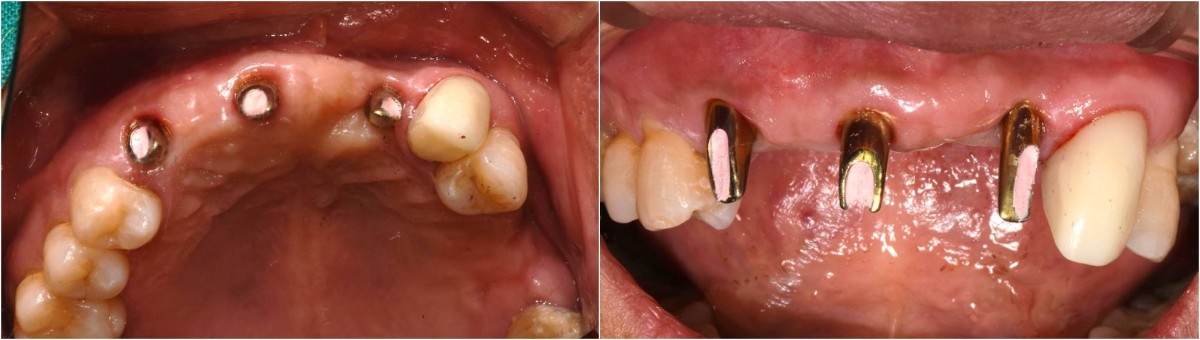

In the anterior maxilla, implant-supported fixed partial denture.

<GCpbc> A 58-year-old male is a patient undergoing implant installation in various parts. The old Br of the anterior maxilla has fallen

off and it is no longer possible to maintain it even temporarily, so a

treatment plan for the anterior teeth was made.